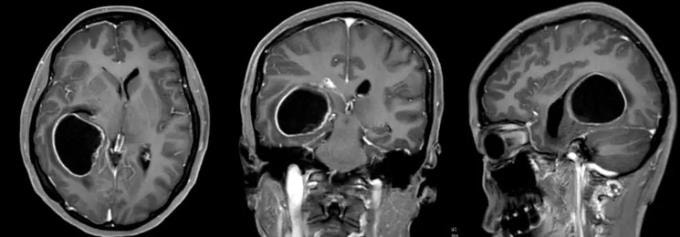

Kết quả chụp chiếu trước phẫu thuật của bệnh nhân Lâm. Ảnh: Ycwb

Bác sĩ Đặng Thiếu Dũng tiếp nhận Lâm trong tình trạng nôn mửa liên tục và lơ mơ. Kết quả MRI xác nhận khối u gây não úng thủy. Êkíp khoa Ngoại thần kinh VII lập tức hội chẩn và quyết định phẫu thuật cắt bỏ khối u. Trưởng khoa Ngô Thái Hoa trực tiếp bóc tách hoàn toàn khối u dọc theo vùng biên tổn thương, đồng thời bảo tồn nguyên vẹn cấu trúc não thất bên. Suốt ca mổ, các bác sĩ dùng hệ thống điện sinh lý thần kinh giám sát liên tục nhằm đảm bảo độ chính xác cao nhất.